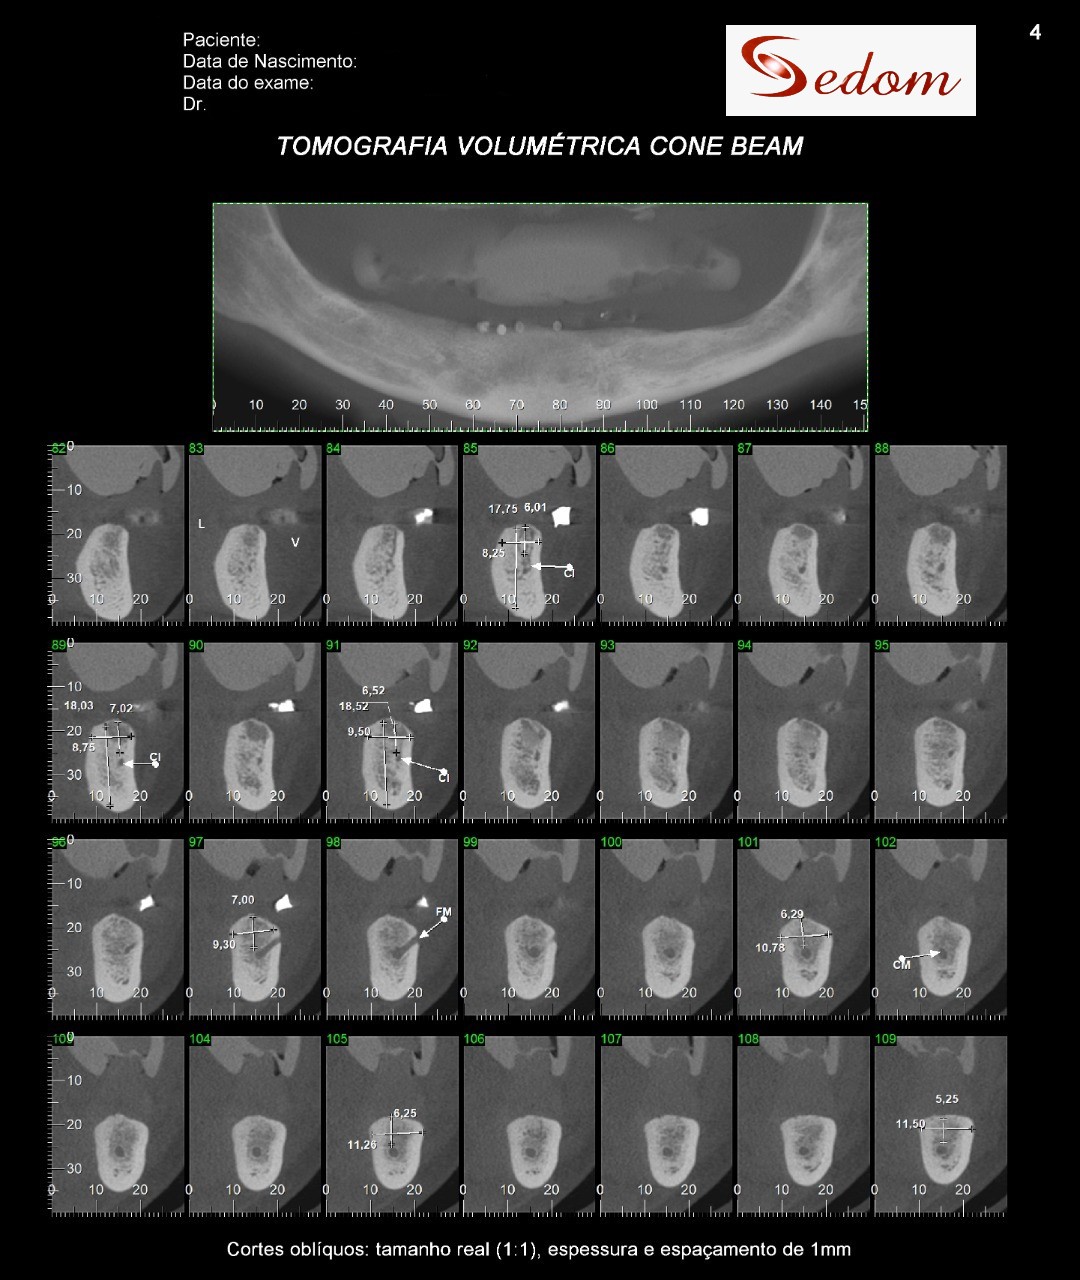

Tomografia Computadorizada

Exame Tridimensional dos maxilares

Tomografia para endodontia

Implantodontia e demais áreas odontológicas